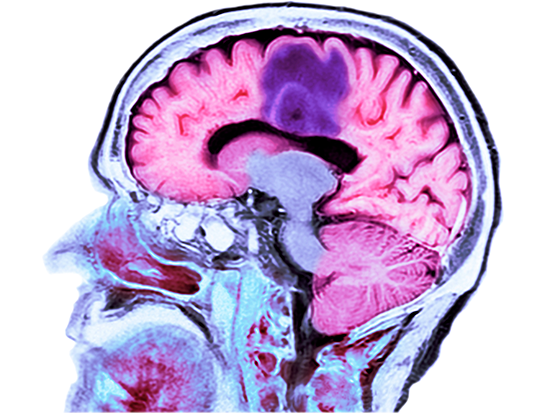

All of the newly diagnosed glioblastoma multiforme patients enrolled in a Phase 1 clinical trial have exceeded both their median and expected progression-free survivals. Two patients, to date, have exceeded their expected overall survival.All of the newly diagnosed glioblastoma multiforme patients enrolled in a Phase 1 clinical trial at the University of Alabama at Birmingham have exceeded both their median and expected progression-free survivals. Two patients, to date, have exceeded their expected overall survival. Glioblastoma multiforme is the most aggressive type of cancer originating in the brain.